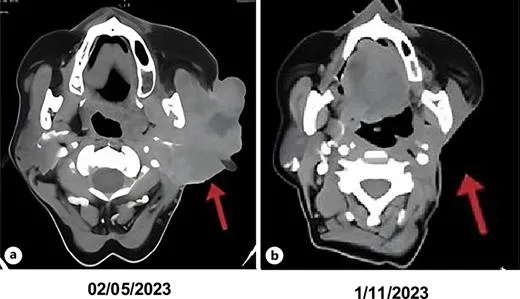

2023年4月,M女士正式开始服用恩曲替尼,每天400mg,简单的口服方式,没有化疗时的痛苦输液。让所有人都没想到的是,疗效来得如此之快:服药13天后,她感觉脸颊的肿胀开始消退,用手摸上去,原本坚硬如石头的肿瘤变软了;49天后复查,肿瘤体积已经缩小了大半,左侧面部的麻木感减轻,嘴角歪斜的情况也有所改善;约6个月的CT检查更是带来了惊喜——肿瘤完全消失,达到了临床完全缓解!截至病例随访结束,这种良好的疗效已经持续了10个月,M女士不仅恢复了正常的饮食和说话功能,还能每天出门散步、帮家人做家务,彻底摆脱了肿瘤的阴影。